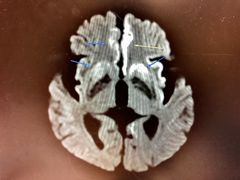

CJD의 증상은 뇌에 비정상적인 프리온 단백질이 축적되어 뇌 신경 세포가 점진적으로 세포 사멸되면서 발생한다. 환자의 뇌 조직을 현미경으로 검사하면 신경 세포가 죽은 곳에 많은 작은 구멍이 보인다. 프리온이 뇌의 특정 부위를 감염시킨 경우, 뇌의 일부가 스펀지처럼 보일 수 있다.[17]

- -|]]|]]|thumb|240px|자기 공명 영상(MRI)을 통해 뇌에서 프라이온 단백질의 명백한 침전을 볼 수 있다.]]

뇌 영상 검사는 다른 원인을 배제하고 진단을 뒷받침하는 증거를 얻기 위해 수행될 수 있다. 뇌 MRI는 CJD와 관련된 변화를 감지하는 데 가장 유용한 영상 검사 방식이며, 이 중 확산 강조 영상(diffusion-weighted imaging) 시퀀스가 가장 민감하다.[48] 특징적인 소견은 다음과 같다.

- 대뇌 피질 및/또는 기저핵을 포함하는 국소적 또는 광범위한 확산 제한. 가장 특징적인 피질 이상은 MRI에서 피질에 리본과 유사한 과다 신호가 나타나는 "피질 리본" 또는 "피질 리본 징후"이다.[49]

- 기저핵(예: 꼬리핵 및 렌즈핵)과 덜하지만 창백핵 및 후두엽 피질에서 나타나는 다양한 정도의 대칭적인 T2 과다 신호 변화.[46]

- -|thumb|240px|MRI를 통해 뇌 내에 프리온 단백질이 침전된 것을 확인할 수 있다.]]